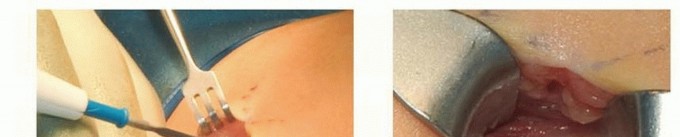

## For the femur, a 1.5-cm vertical incision is made, starting at the tip of the greater trochanter and extending proximally (FIG 7A).

## The tensor fascia is then incised, exposing the greater trochanter (FIG 7B).

## A 1-cm incision is made directly over the anterior lateral apex of the deformity.

## Blunt dissection then is performed with a hemostat down to the periosteum (TECH FIG 1C).

## The periosteum is incised longitudinally with a small osteotome, which is then rotated 90 degrees (TECH FIG 1D).